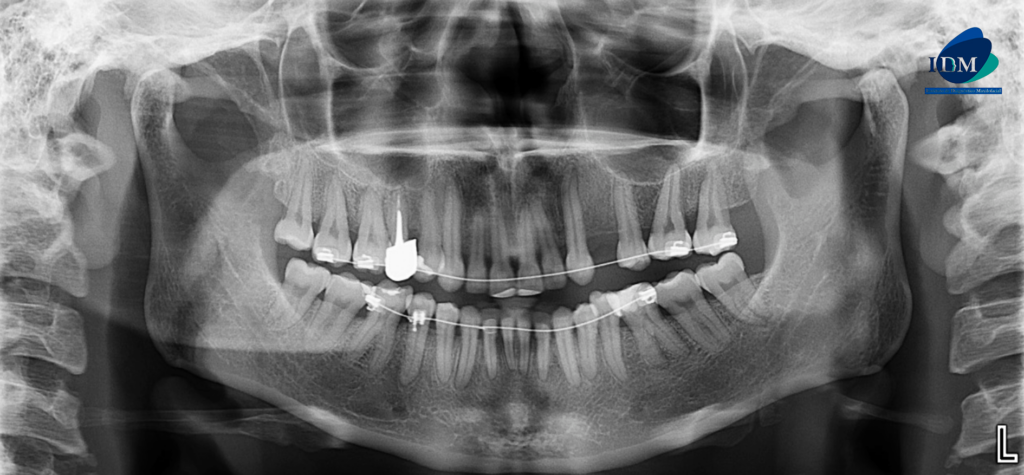

RECONSTRUCCIÓN 3D

A la evaluación de la tomografía volumétrica (cone beam) en los cortes axiales (Figura 2), tangenciales (Figura 3) y en la reconstrucción 3D (Figura 4) se observa en la pieza 47 la configuración del conducto radicular en forma de “C” desde tercio cervical hasta apical.

- Taurodontismo en pieza 37 y 47.

- Conducto radicular en forma de “C” en pieza 47.